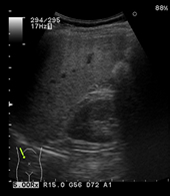

頸動脈の超音波検査

頸部にゼリーを塗り超音波をあてて、画面に頸動脈を映し出し血管壁や血流を観察します。

血管壁の厚さや血管壁にコレステロールなどが沈着したプラークと呼ばれる壁隆起の数、

大きさ、形状などを参考に動脈硬化の進行の程度や脳梗塞、心筋梗塞の発症の危険性を判定します。

正常頸動脈

動脈硬化が進行した頸動脈